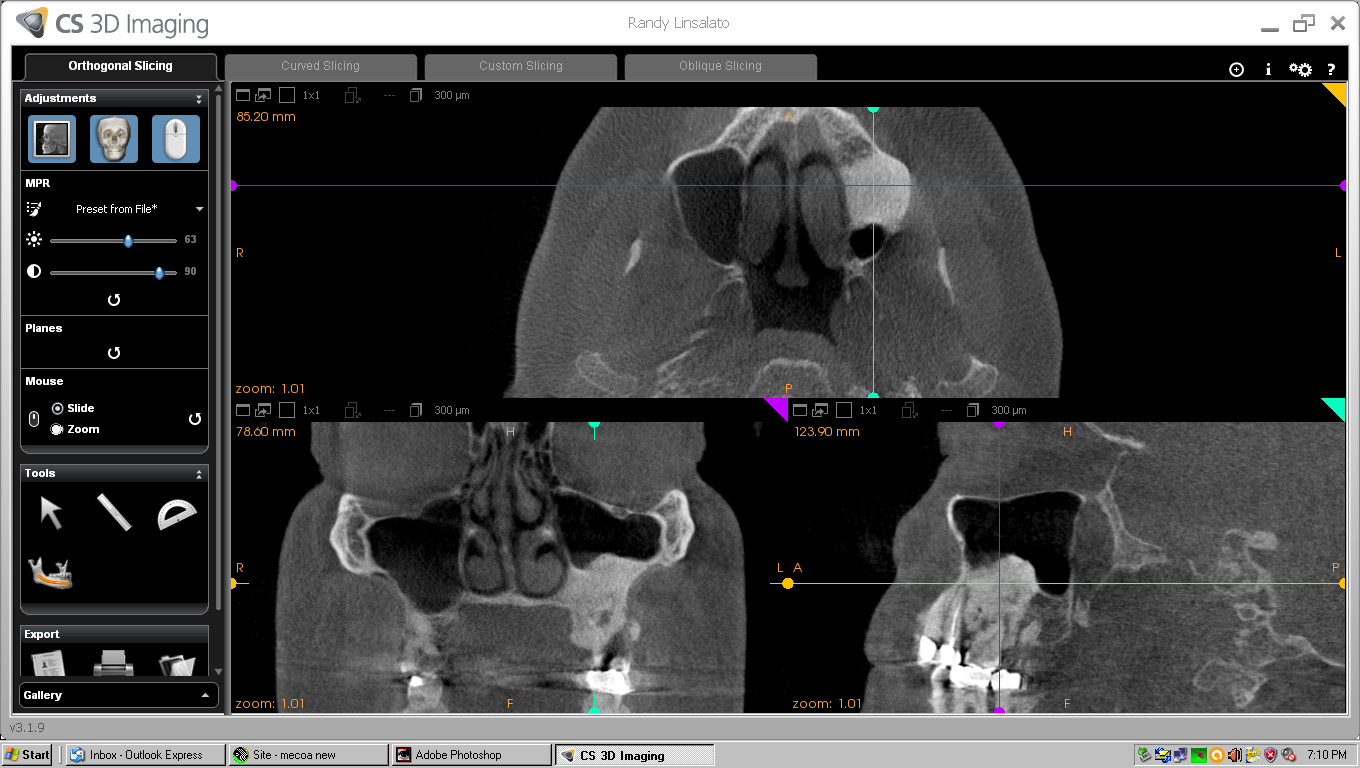

He took the scan below to see the extent of the Osteoma.

As you can see the dense bone mass extends from my lower sinus down around the roots my teeth 14 and 15

Involvement of teeth 13,14, and 15 is obvious.